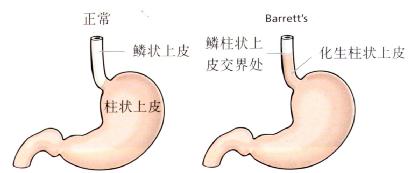

Barrett食管是慢性GERD的一种并发症。为更好地抵抗反流物的损伤,食管远端的正常鳞状上皮被化生的柱状上皮所取代(图3.17)。

图3.17Barrett食管。